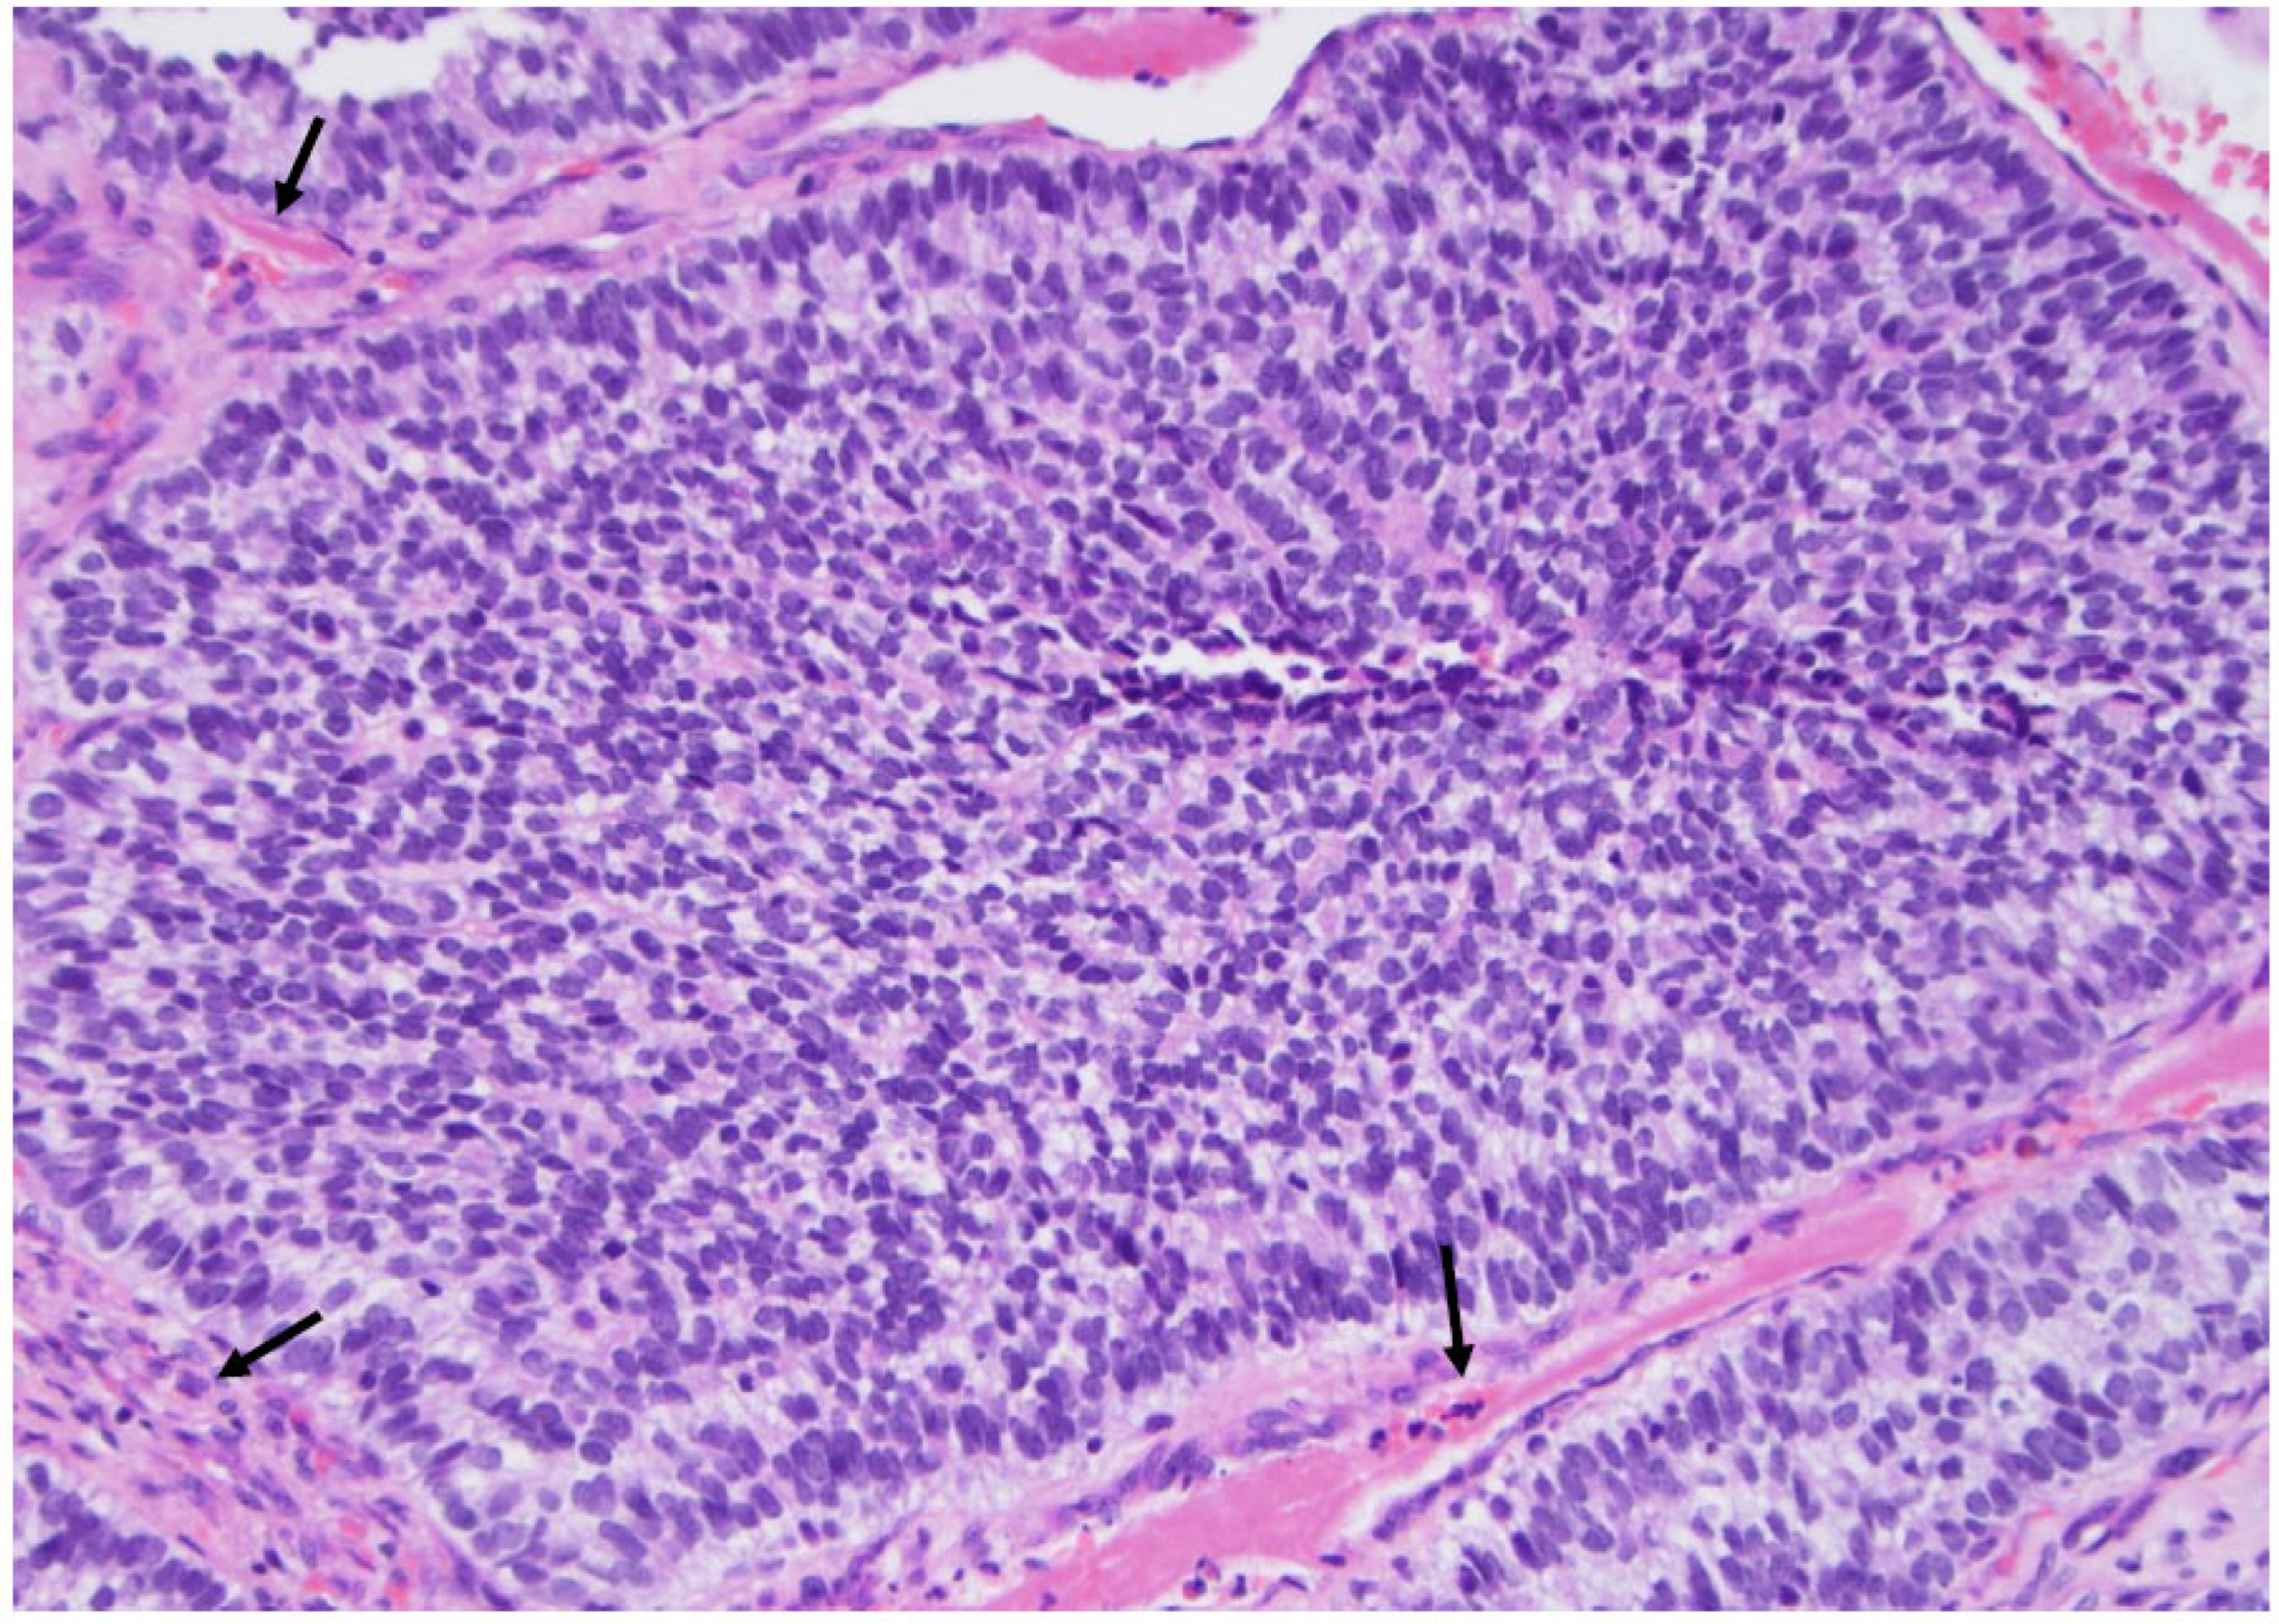

Figure 11. Medullary thyroid carcinoma: note the necrotic area (arrows), indicating a high-grade medullary carcinoma diagnosis (×200, H&E stain).

The most significant update for medullary thyroid carcinoma (Figure 9) is the introduction of a grading system called “the International medullary thyroid carcinoma grading scheme”. This is a two-tiered grading system; high-grade cancers are characterized by tumor necrosis; a mitotic count ≥ 5 mitoses per 2 mm2; and/or a Ki 67 proliferation index ≥ 5% (Figure 10 and Figure 11) [10].